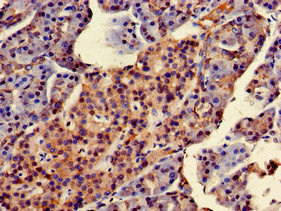

Immunohistochemistry of paraffin-embedded human pancreatic tissue using CSB-PA853100LA01HU at dilution of 1:100